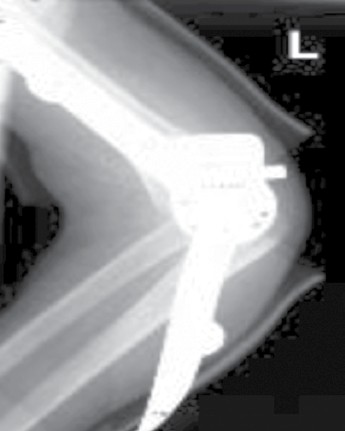

Das Therapieziel ist wie oben beschrieben das Erreichen der Selbstständigkeit, d. h. insbesondere die Hand-Mund-Koordination für die Nahrungsaufnahme. Aber auch sonstige alltägliche Funktionen, insbesondere für das ältere Kind, wie Schreiben, Malen, Körperhygiene oder erste Arbeiten an einer Computertastatur sollen ermöglicht werden. Hierzu kann es auch notwendig sein, einen Arm in die Beugung zu beüben und den anderen in die Streckung, um die genannten Funktionen zu erreichen, da die Gesamtbeweglichkeit eines Gelenkes bei AMC kaum über 20° Gelenkexkursion hinaus verbessert werden kann. Die Orthesen an der oberen Extremität werden mit separaten zirkulären Oberarm‑, Unterarm- und Handfassungen angefertigt. Über den Drehpunkten der jeweiligen Gelenke, insbesondere am Ellenbogen, werden Caroli-Quengelgelenke angebracht. Caroli-Gelenke sind einstellbare Orthesengelenke, die eine Art Zahnradscheibenaufbau haben und zum Dehnen bzw. Quengeln bei Gelenkkontrakturen verwendet werden. Die korrekte Lage der integrierten Orthesengelenke sollte stets im Röntgen mit angelegten Orthesen überprüft werden (Abb. 1).

Die Therapie von Kindern mit einer Arthrogrypose ist umfangreich. Der Kinderorthopäde leitet die Behandlung bereits in den ersten Lebenstagen mit täglicher Physiotherapie und häuslichen Dehnübungen ein. Während im ersten Lebensjahr v. a. Gipsschälchen angepasst werden, kommen ab dem ersten Lebensjahr Orthesen zum Einsatz, die jeweils mindestens 6 von 24 Stunden getragen werden müssen, da ansonsten die Kontrakturen im Wachstum zunehmen. Die Orthesen an der oberen Extremität werden mit separaten möglichst ringförmigen Fassungen für Oberarm, Unterarm und Hand angefertigt. Auch an den Beinen bekommen sowohl Ober- als auch Unterschenkel eine separate Fassung. Die Füße werden ringförmig gefasst. Über den Gelenken werden Quengelgelenke eingebaut, deren Lage radiologisch überprüft werden muss. Ziel ist der Erhalt von Gelenkbeweglichkeit und ‑funktion und damit die Förderung der Selbstständigkeit und des Selbstbewusstseins.